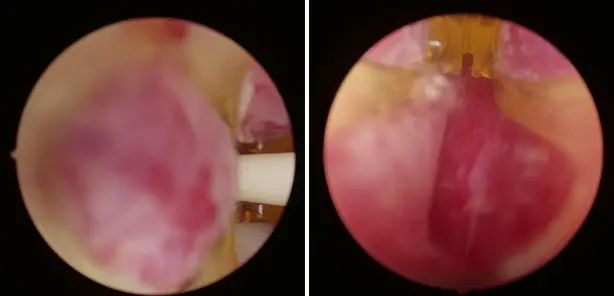

전립선비대증 치료에 있어 리줌 수술의 효과를 잘 보여줍니다.

천안 굿모닝비뇨기과는 기존의 전통적인 수술방법(경요도적 전립 선절제술;TURP, 광선택적 전립선기화술;KTP PVP, 전립선 홀뮴레이저 수술;HoLEP 등) 뿐만 아니라 리줌(REZUM), 전립선 결찰술(Urolift), 프로게이터(Pro-Gator)등 을 포함한 최소 침습적 수술방법도 가능하여 환자분의 상태와 상황에 맞춘 맞춤형 치료를 진행할 수 있습니다.